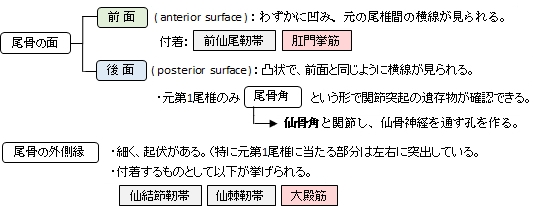

・全体としては逆三角形の形を呈する。

・第1尾椎にあたる部分の下から第1尾椎神経が出るが、それ以下からは神経は出ない。 ・仙骨と骨化(ossification)しない場合は、椎間円板を介して関節する。(仙尾関節)

「日本人体解剖学 (上巻) 」では「尾骨の筋」として以下の3つの筋を挙げている。

起始とする筋肉群 |

停止とする筋肉群 |

1 |

大殿筋(外側縁) |

1 |

尾骨筋(外側縁) |

2 |

外肛門括約筋(尾骨先端) |

2 |

前仙尾筋(前面) |

3 |

後仙尾筋(後面) |

||

4 |

肛門挙筋(尾骨先端) |

以下に尾骨に付着する靭帯を挙げたが、過不足が生じる可能性もある。

仙腸関節(2) |

sacrotuberous ligament | 坐骨結節と尾骨、仙骨、下後腸骨棘を結ぶ | |

| sacrospinous ligament | 坐骨棘と仙骨・尾骨の外側縁を結ぶ | ||

仙尾関節 (3) |

ventral sacrococcygeus l. | 仙骨と尾骨の前面を結ぶ | |

| dorsal sacrococcygeus l. | 仙骨と尾骨の後面を結び、浅・深に分かれる | ||

| lateral sacrococcygeus l. | 仙骨尖の側縁と第1尾椎の横突起を結ぶ | ||

その他(1) |

interspinous ligament | 椎骨の棘突起間を結んでいる |